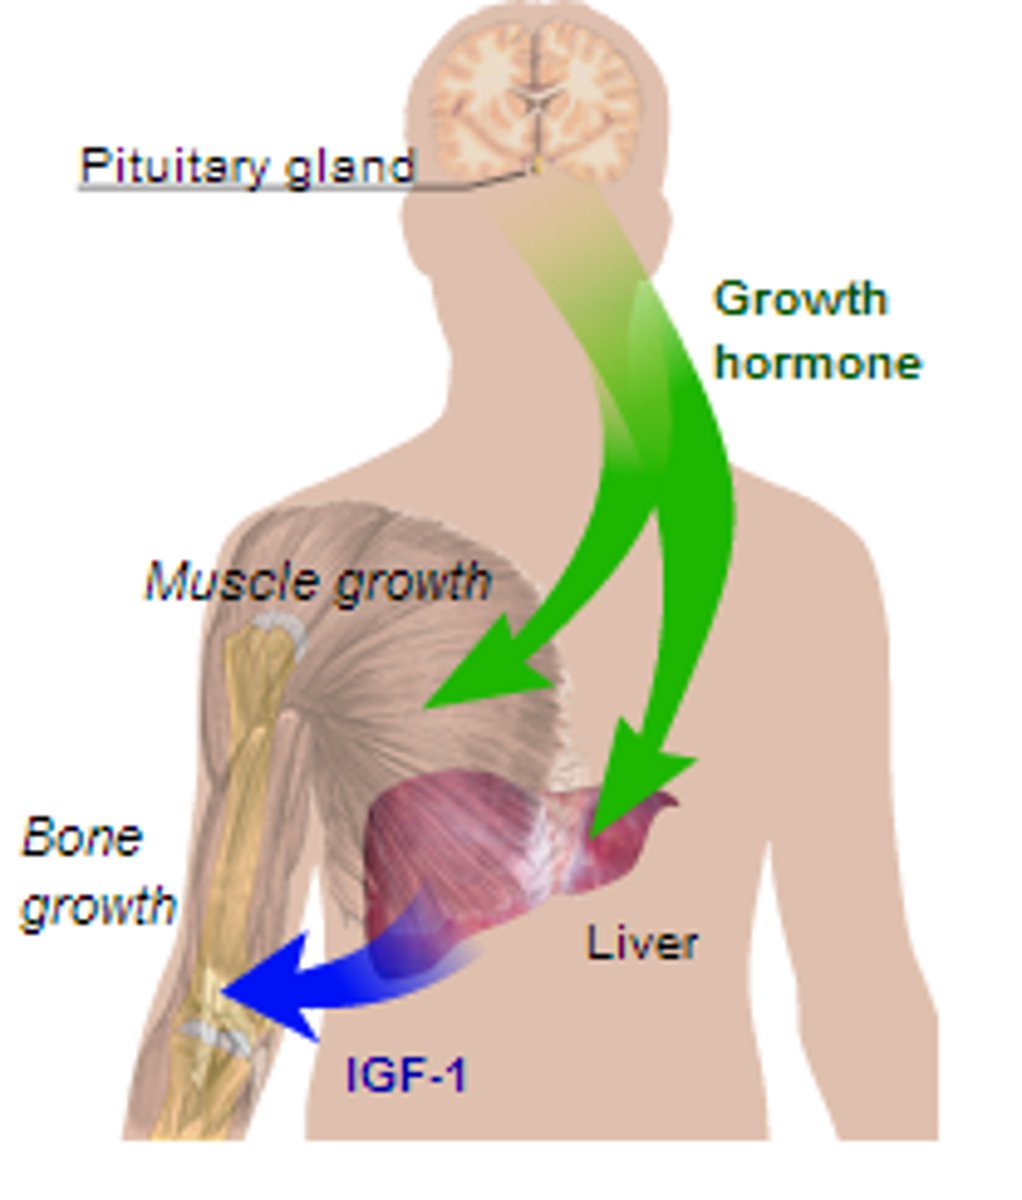

Hormones

chemicals released into the bloodstream that

control many body functions, such as growth, repair and reproduction